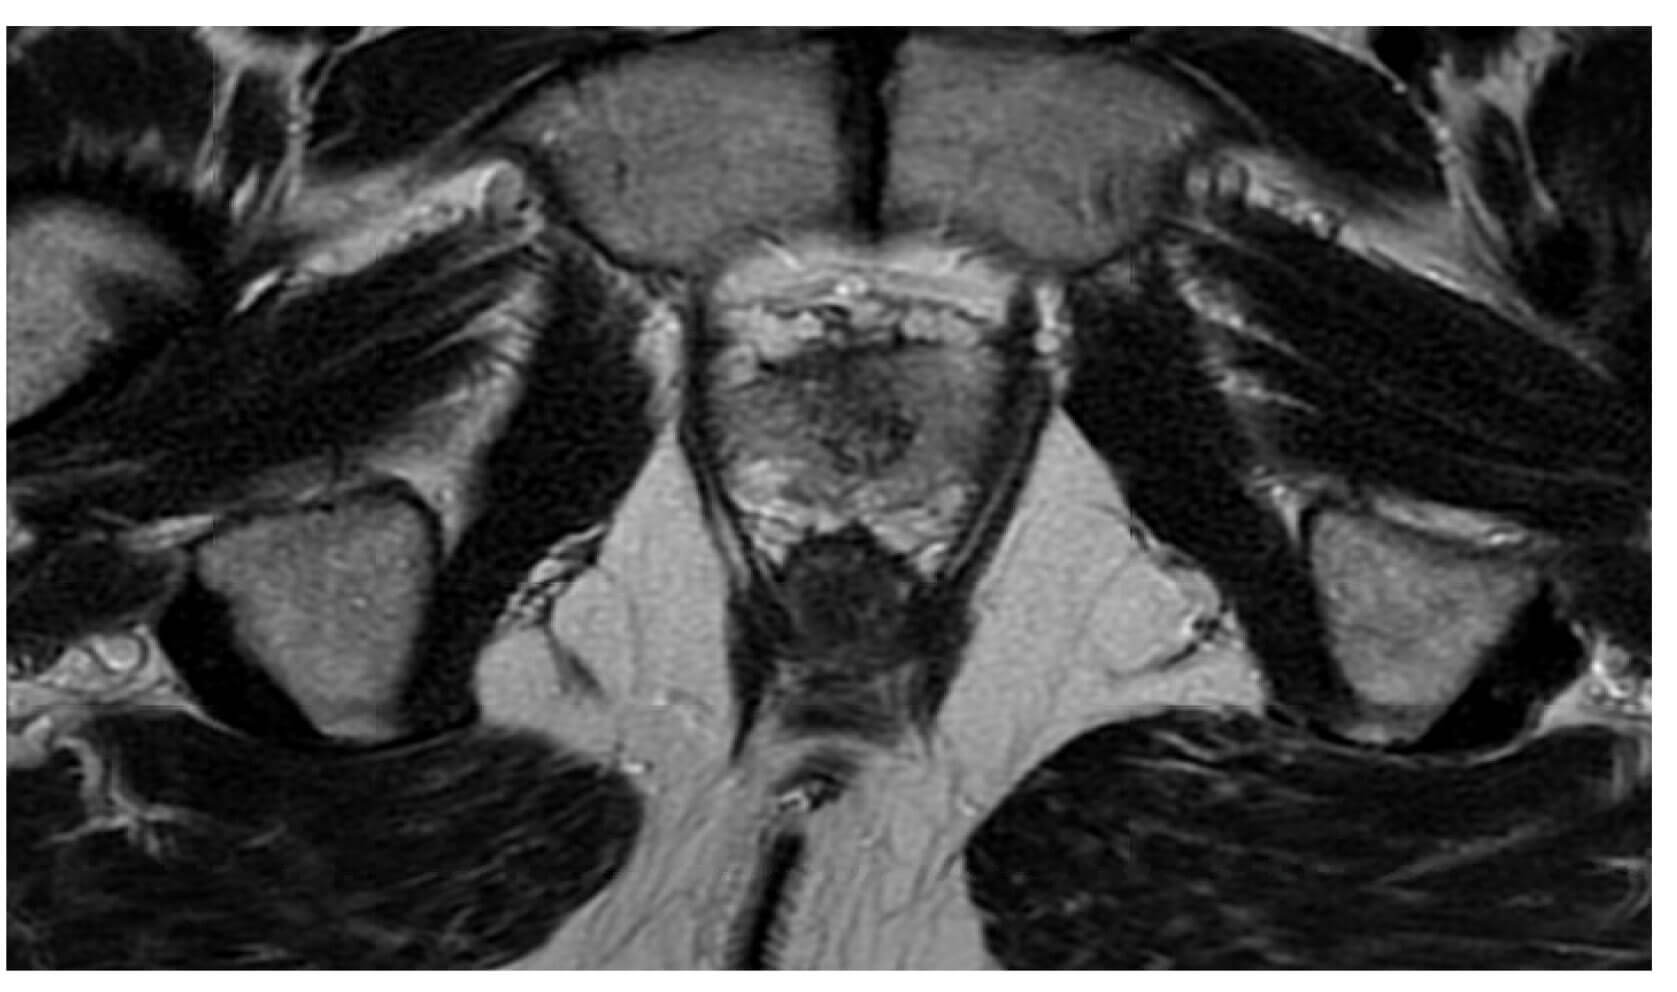

Days after a treatment course was completed for the above UTI, the patient’s groin symptoms became intolerable, and he was admitted to hospital for management. A CT scan was performed to rule out a pelvic collection, and a flexible cystoscopy was performed followed by bladder catheterisation. The cystogram showed no leak, but the CT scan suggested osteomyelitis (Figure 2a). An MRI pelvis (Figure 2b) was requested in order to confirm or refute the presumptive diagnosis made on CT. The MRI report concluded that changes seen in the bone were that of infective osteitis pubis and osteomyelitis. There was also an associated small amount of enhancing fluid at pubic symphysis posteriorly along with mild oedema of right obturator muscles.

Figure 2b: Post RARP MRI T1 post contrast showing bone marrow signal change and

enhancement around the pubic symphysis. Oedema of the right obturator muscles.